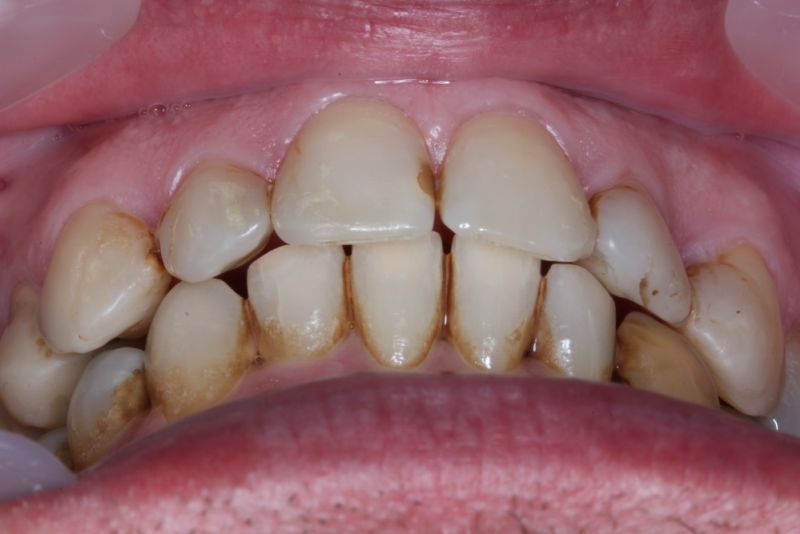

Der Patient hat in den Jahren 2012-2014 eine kieferorthopädische Erwachsenenbehandlung durchführen lassen.

Erkennbar ist die massive Abweichung der habituellen Bisslage von der neuromuskulär zentrierten Bisslage.